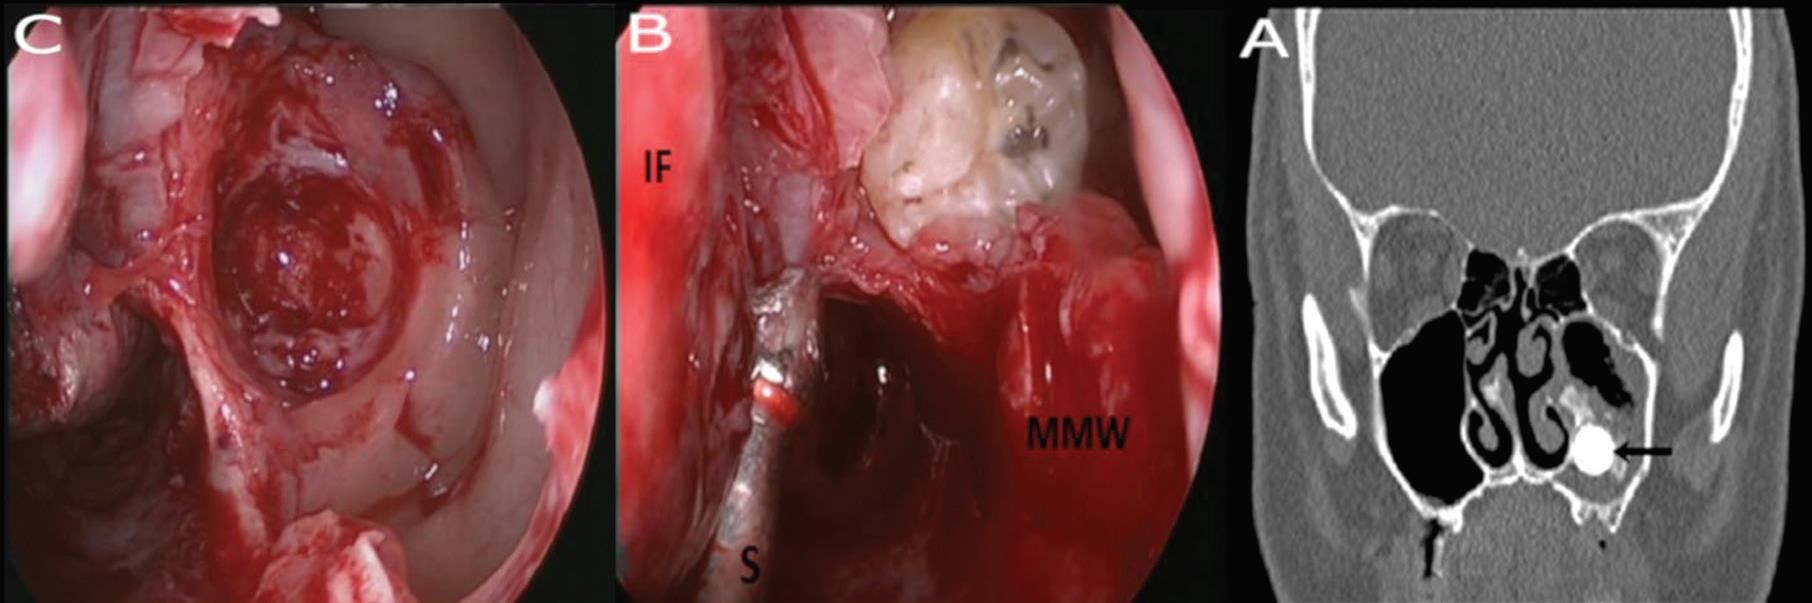

לאחר מספר בדיקות שעבר במקום, התגלתה הסיבה המפתיעה שגרמה לבעיה: שן שצמחה בחלל הסינוס המקסילרי מצדו השמאלי של האף שיצרה ציסטה דנטלית גדולה מאוד. בניתוח אנדוסקופי זעיר פולשני שבוצע ללא חתך חיצוני, אלא דרך הנחיריים, ד"ר מוחמד מסאלחה, מומחה לניתוחים אנדוסקופיים של האף, סינוסים ובסיס הגולגולת, ביצע פתיחה של מערת הלסת משמאל לחלל הסינוס המקסילרי – וכך נעקרה השן. הד"ר מסביר כי השן הוצאה בשלמותה דרך האף, הציסטה רוקנה מהדלקת והאזור נוקה וטופל. למחרת, שוחרר יוני לביתו ותוך שבוע, חלפו הכאבים.

"לאבחנת המחלה דרושות בדיקות דימות. צילום רנטגן פשוט המכוון לסינוסים, יכול לאבחן את נוכחות השן בחלל הסינוס. אולם, על מנת לקבל אבחנה ודאית הכוללת מיקום מדויק של השן, גבולותיה, גבולות מערת הלסת והיקף התהליך הדלקתי, דרושה בדיקת CT לסינוסים ולסת עליונה, הנחשבת לבדיקה העדיפה לצורך אבחון שיניים אקטופיות בסינוס המקסילרי ובאבחנת סינוסיטיס. בדיקה כזו, ניתן לבצע באמצעות מכשיר CBCT, מכשיר CT בעל קרינה מינימאלית, הייעודי למצבים בריאותיים אלה, הנמצא במרכז הרפואי א.ר.ם. לאחר האבחנה, הטיפול כירורגי.

ד"ר מסאלחה מציין כי בעבר טופלו מקרים מסוג זה על ידי רופאי שיניים או מנתחי פה ולסת, לרוב היה מדובר במטופלים שאובחנו במקרה, במהלך בירור דנטלי. הטיפול כלל גישה כירורגית דרך חלל הפה, על ידי חתך כירורגי מעל רכס השיניים בצד המעורב, חדירה למערת הלסת, עקירת השן וניקוי הסינוס. אולם, עם התפתחות הגישה האנדוסקופית, בשני העשורים האחרונים, יותר ויותר מקרים של שיניים אקטופיות טופלו בגישה זו, דרך חלל האף. במהלך השיטה, רופא אא"ג המומחה למחלות האף והסינוסים (רינולוג) משתמש בסיבים האנדוסקופים יחד עם ציוד כירורגי דק ומיוחד, כדי לפתוח את הסינוס החולה, לעקור את השן האקטופית ולנקות את הסינוס לחלוטין. "מדובר בשיטה זעיר פולשנית ללא חתכים חיצוניים, הכרוכה בכאבים קלים בלבד המשפרת את הסיכוי לריפוי הסינוס באופן פיזיולוגי טוב וללא סיבוכים. בנוסף, הגישה האנדוסקופית משמרת את ריריות הפה ואת האנטומיה הדנטלית כפי שהן, מה שמקל על כל תהליך טיפולי או שיקומי דנטלי בעתיד", מציין הד"ר.